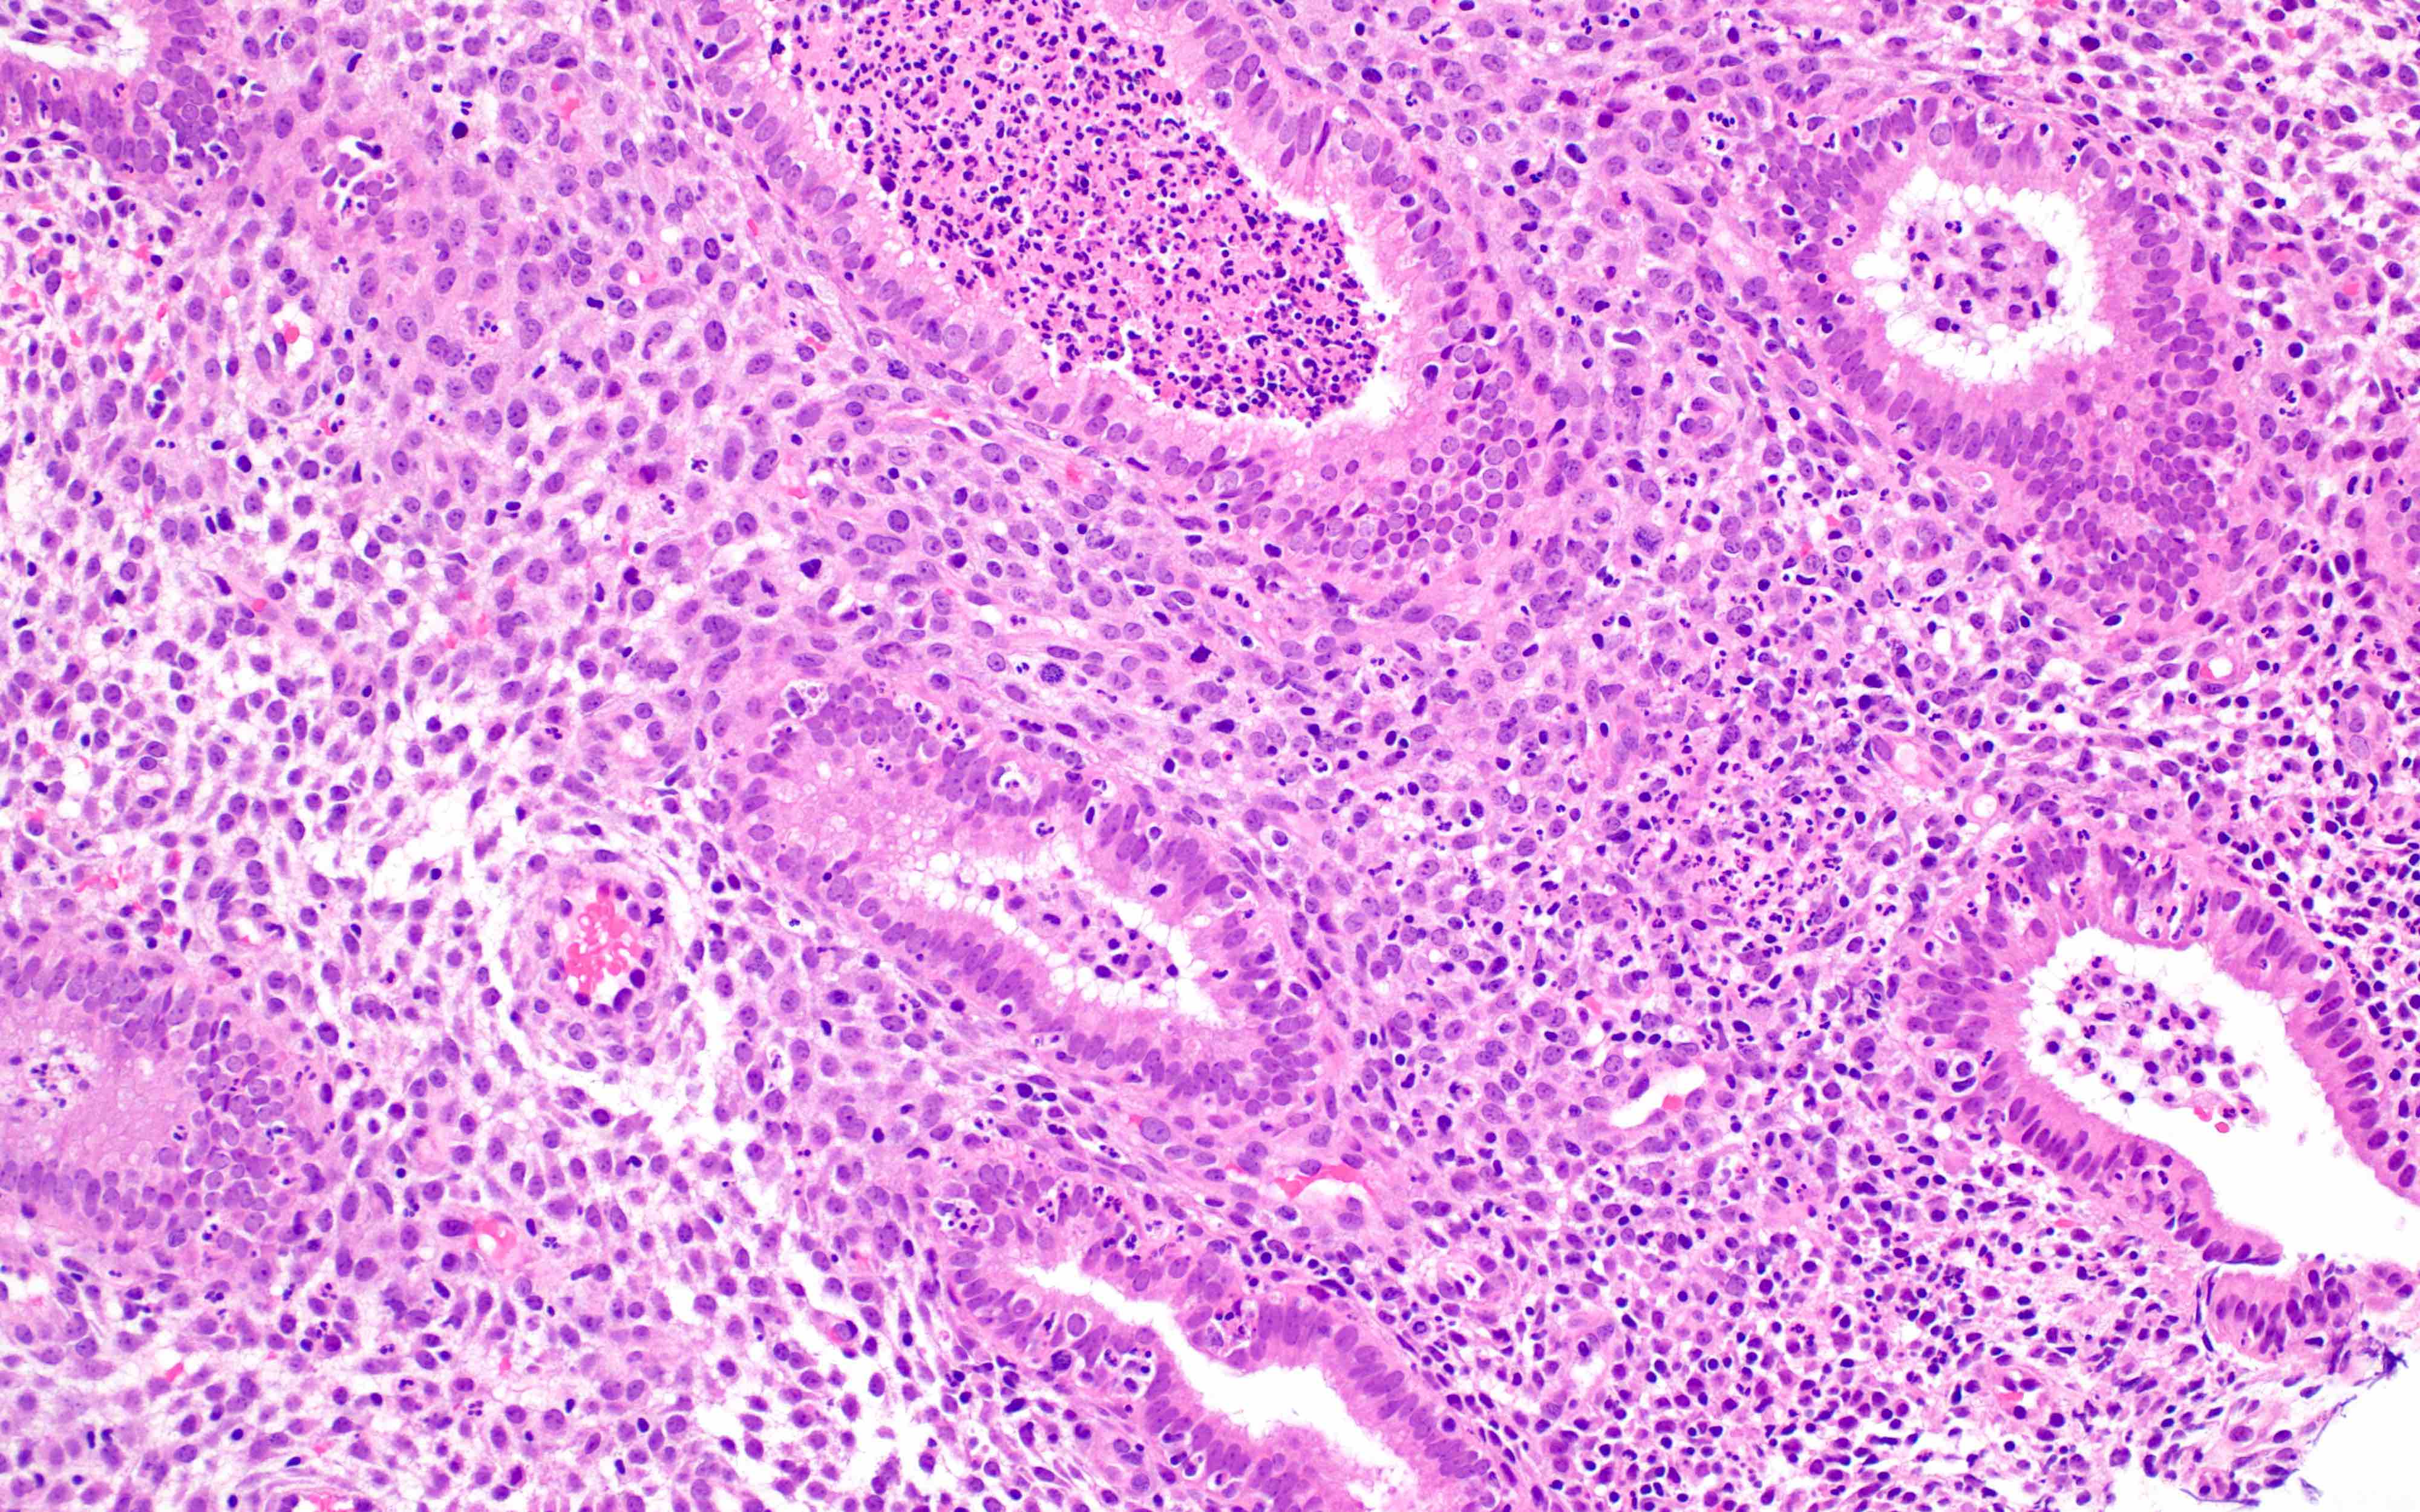

Microscopic (histologic) images

Contributed by Stephanie L. Skala, M.D. and Yuri Tachibana, M.D.

Chronic endometritis

Xanthogranulomatous endometritis